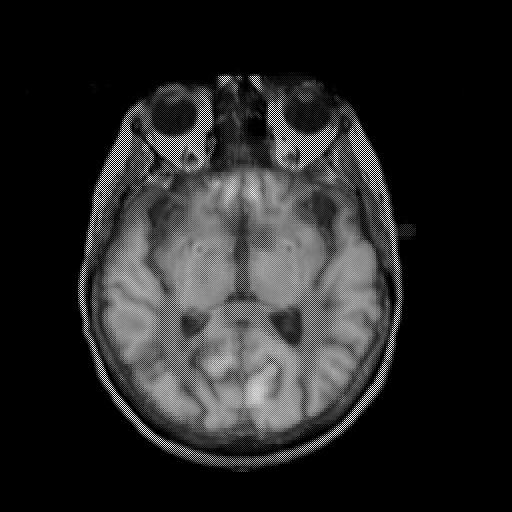

overlay: Slice 26

Slice 26

MRCBFCBF with

T1PDT2T1PDT2